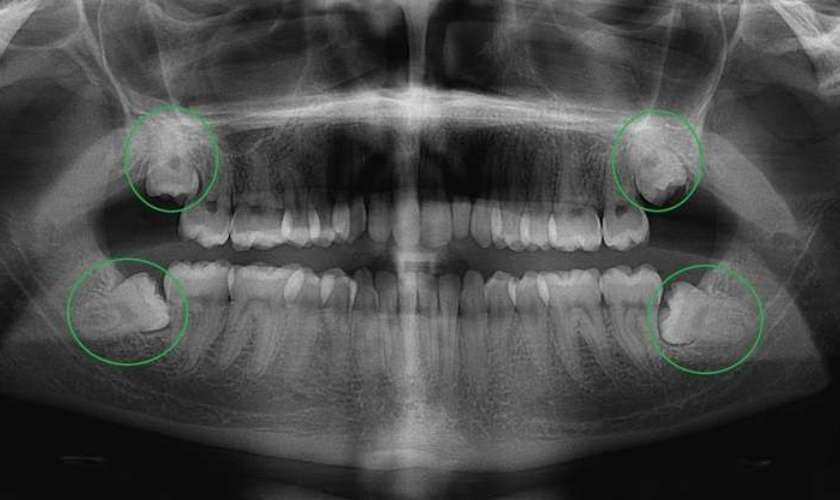

Kỹ thuật này cho phép chụp toàn bộ khoang miệng, bao gồm hàm, răng, xoang mũi và khớp thái dương. Chụp X-quang toàn cảnh răng cung cấp cái nhìn tổng quát nhất và giúp chẩn đoán các vấn đề như sâu răng, khối u, áp xe, răng mọc lệch, tổn thương xương hàm và nhiều vấn đề khác.

- Răng khôn: Chụp X-quang răng khôn giúp đánh giá vị trí, hình dạng và tác động của răng khôn đến xương hàm và các răng khác.